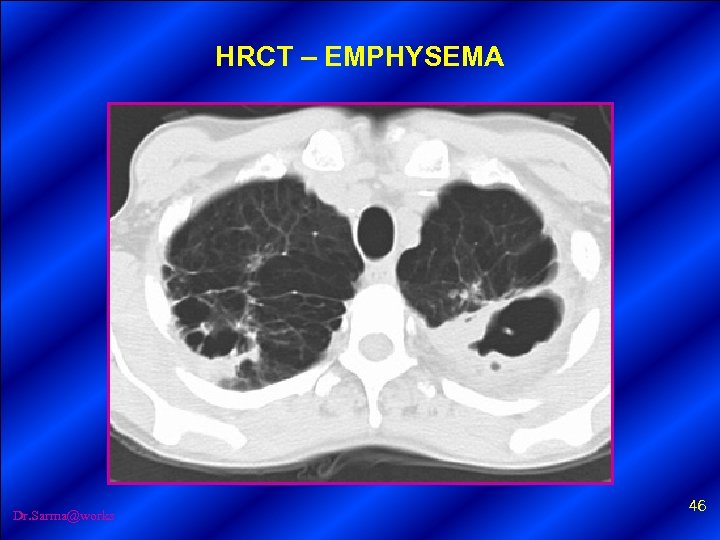

HRCT – NORMAL CHEST Dr. Sarma@works 45

HRCT – EMPHYSEMA Dr. Sarma@works 46